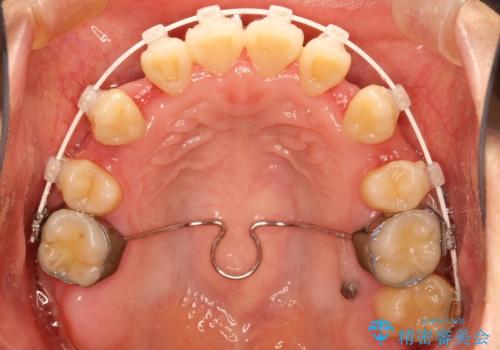

- 矯正装置

- 審美装置

がたつきの度合いが強いのと、口元をなるべく引っ込めたい希望がありましたので、ワイヤーでの抜歯矯正となりました。

ガタガタが重度の方は抜歯が必要となることが多いです。

抜歯スペースを使って前歯を引っ込めることにより、口元の突出感も改善できました。